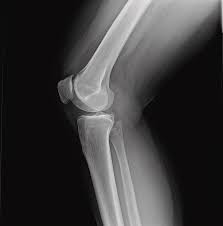

Some of you have even seen me unable to move away from my teaching mat as the knee joint I am so protective of, locks and I am immobilised.

As part of my recovery, I started to research Yoga for my knee injury, I knew Yoga could help me recover if I gave it the chance, and alongside other therapies, my knee injury (A Medial Collateral Ligament tear) is almost healed, I know there are things still beyond my ability at the moment, but I know in time, they will come back to my practice, and until then, I will continue to strengthen other parts of my body, I will build my breath, and explore my mind.